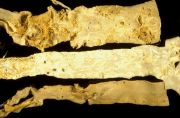

| 2021年12月10日 (五) 13:24 | 27号切片-胃溃疡-大体观.jpg (文件) |  |

69 KB | Cirno.9 | 基于MsUpload的文件上传 | 1 |